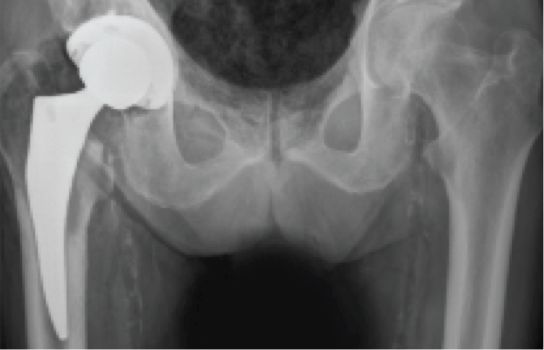

Mako Robotic-Arm Assisted Total Hip replacement is a surgical procedure intended for patients who suffer from non-inflammatory or inflammatory degenerative joint disease (DJD). Some forms of DJD include osteoarthritis (OA), post-traumatic arthritis, rheumatoid arthritis (RA), avascular necrosis (AVN) and hip dysplasia.